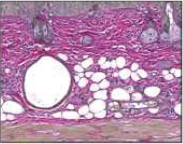

| Collagen |  |  |  |  |

| Elastin |  |  |  |  |